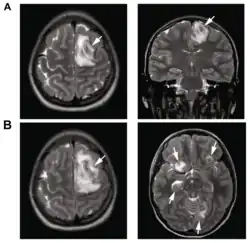

A: T2-weighted MRI showing multiple necrotic brain abscesses as a result of a Balamuthia mandrillaris infection.

B: T1-weighted MRI showing expansion of the brain infection 4 days later